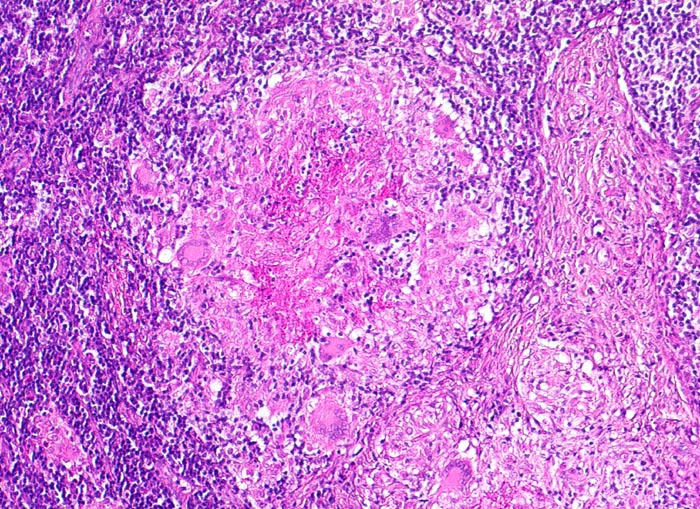

Lymphknotentuberkulose: verkäsendes Granulom und Vernarbung

Links im Bild ein zentral verkäsendes Granulom mit Langhans Riesenzellen. Rechts davon Vermehrung von Kollagenfasern.

Konglomerattumor am Hals mit Fistelbildung bei Patient aus Zimbabwe.

Tuberkulosegranulome können durch zunehmende Produktion von Kollagenfasern vernarben. Die Nekroseareale können verkalken.